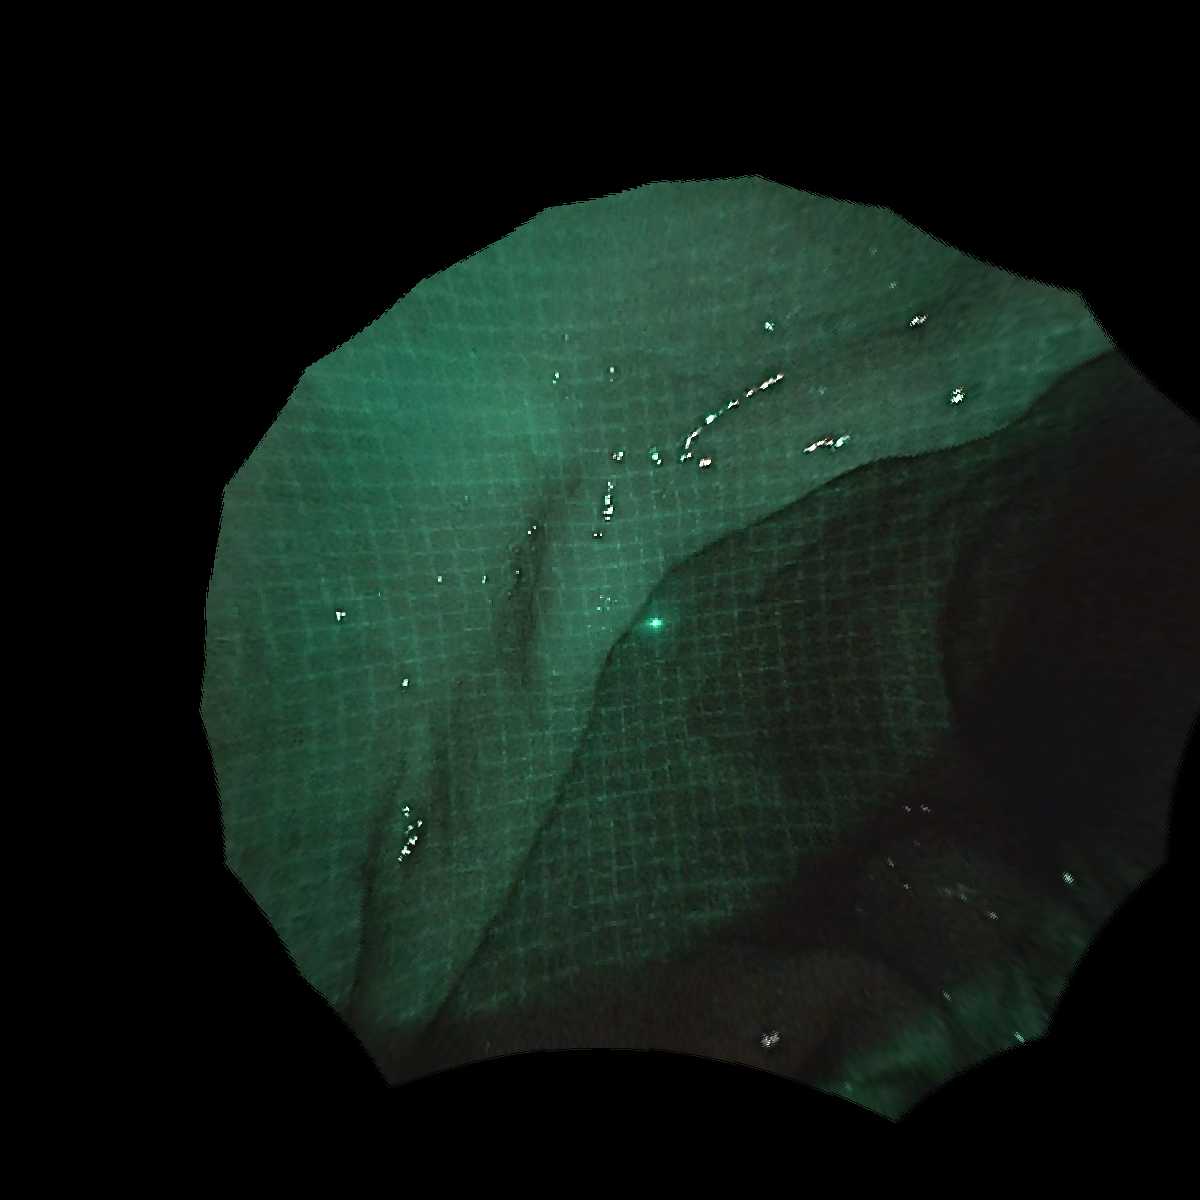

内視鏡の鉗子チャネルに小型パターンプロジェクタを挿入し,

観察対象にパターン光を照射した状態で内視鏡カメラで画像を撮影します.

計測対象は生体組織であるため,組織内の散乱(subsurface scattering)によって投影パターンがぼやけることがあります.

また,内視鏡環境ではノイズや外乱の影響が通常のカメラ環境よりも大きくなります.

これらに対処するため,グリッドパターンのグリッド点をグリッド辺間のギャップで変調するギャップ符号化グリッドパターンと,

DOE(回折光学素子)を用いてシャープにパターンを投影できる超小型パターンプロジェクタを開発しました.

本プロジェクタは画角約90度の広角投影が可能であり,広範囲をカバーできます.

プロジェクタを鉗子孔に挿入することで,

パターンを投影しながら内視鏡撮影を行うことができます.